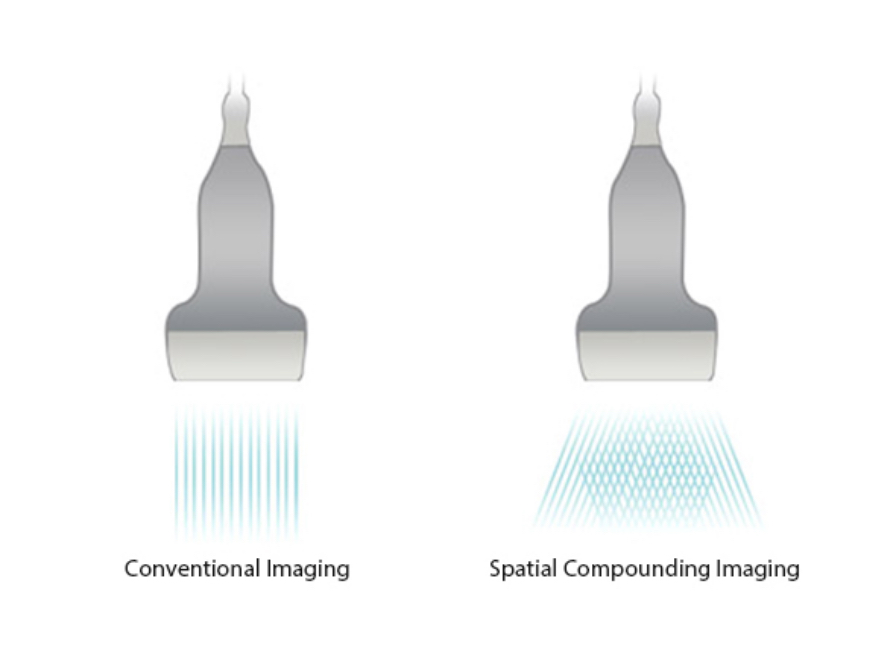

Permits use of multiple scanned angles to form a single image, resulting in enhanced contrast resolution and improved visualization.